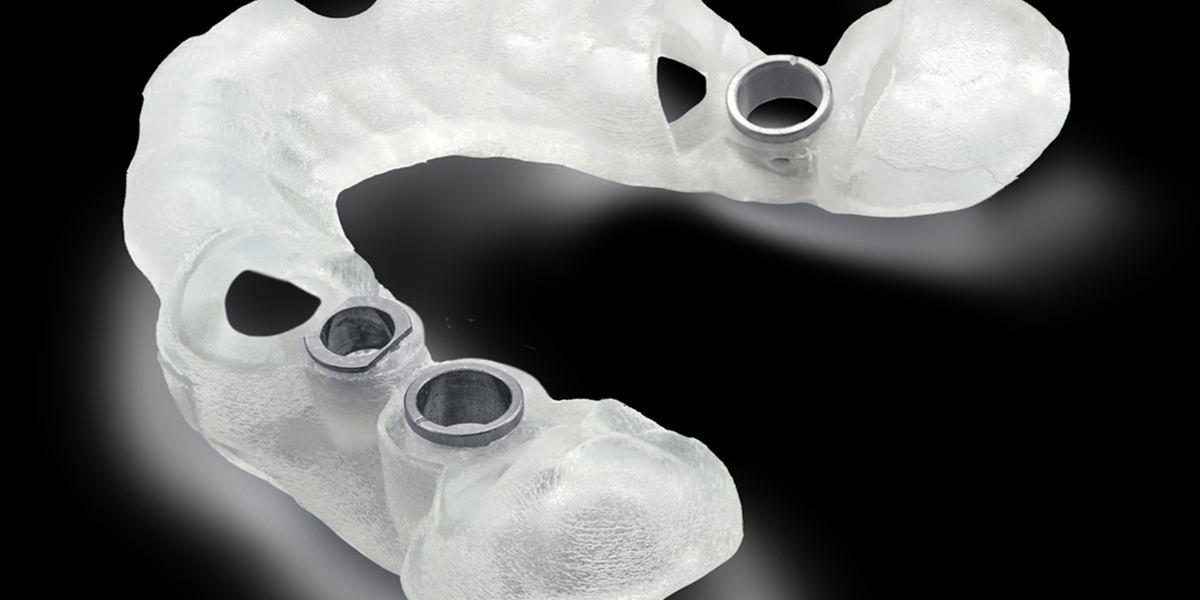

- طراحی گاید جراحی دیجیتال

در نهایت، با استفاده از این دادهها یک گاید جراحی طراحی میشود که محل دقیق کاشت ایمپلنت را مشخص میکند.

- امکان طراحی دقیق گاید جراحی